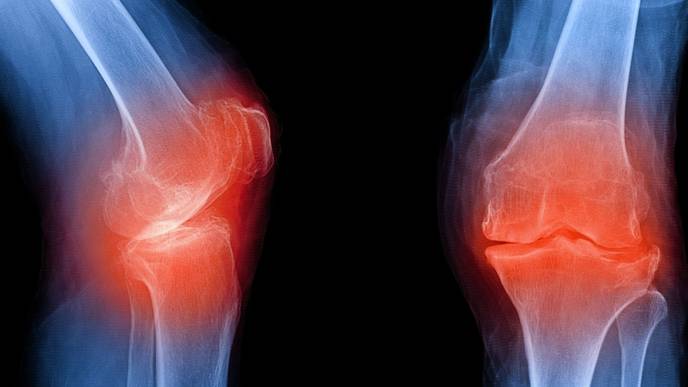

In some cases, the test could predict the disease up to eight years before an X-ray could detect signs of it. This is potentially a big improvement, as X-rays are currently the gold-standard diagnostic approach for osteoarthritis. The researchers say this early detection is important, because although there is no cure for the disease, there are preventative measures that can slow its progression. These include lifestyle factors such as engaging in low-impact exercise and maintaining a healthy weight, and taking medications that can relieve symptoms.

Osteoarthritis is the most common form of arthritis, and it affects more than 32.5 million adults in the U.S. It was originally known as a "wear and tear" disease because it occurs when cartilage within a joint — usually in the hands, hips and knees — breaks down. This causes the underlying bone to change over time, leading to pain, stiffness and swelling.

However, evidence now suggests that inflammation is an integral driver of the joint damage seen in osteoarthritis. This means that there could be "biomarkers," or measurable signs in the body, that could signal that the disease is kicking off long before structural damage is picked up by an X-ray.